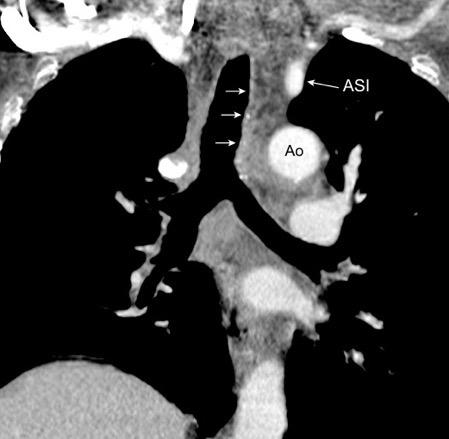

Líneas paraespinales formando un “paréntesis” por encima del diafragma. El signo señala el origen “intratorácico” de la lesión.

Conrad A et al. Pott’s disease associated with large and multiple abscesses in a 30-year-old migrant from Chad. BMJ Case Rep 2018

(lesiones toracoabdominales) La divergencia de las líneas paraespinales apunta a lesión toracoabdominal, que desde el tórax desciende y penetra en el abdomen.

Signo del “iceberg” positivo en Tb vertebral

Afectación por vía hematógena. Región dorsolumbar más frecuente. Afectación inicial: irregularidad de los platillos vertebrales, disminución del disco intervertebral con esclerosis ósea adyacente. Kim. Radiographics.2001